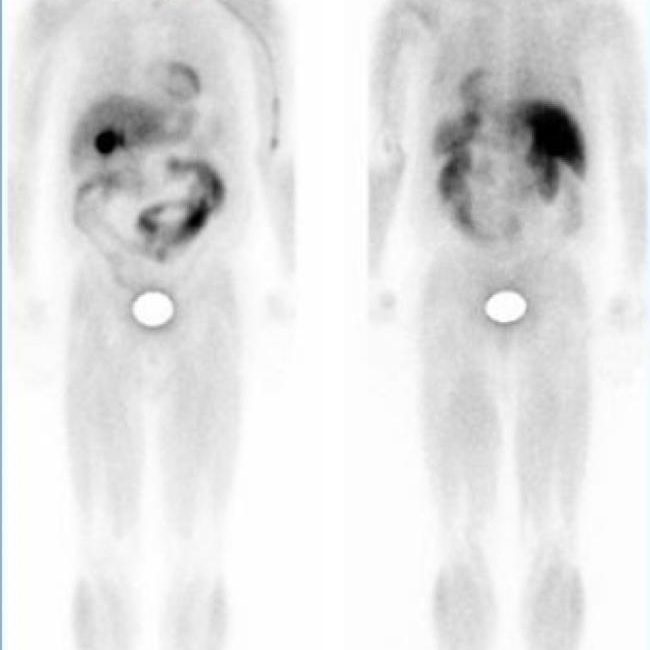

Toma imágenes del marcador que hay en sus huesos. El técnico puede solicitarle que cambie de posición durante el procedimiento. Esto ayuda a obtener imágenes desde diferentes ángulos. Una gammagrafía ósea de todo el cuerpo tarda aproximadamente 1 hora en completarse.